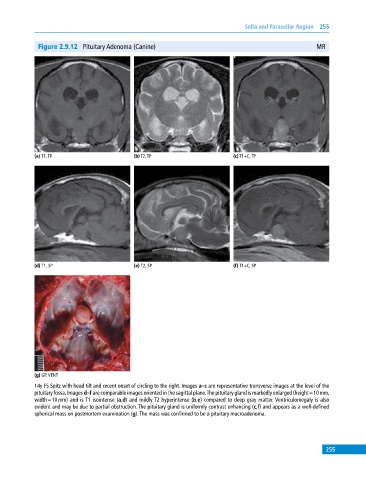

Figure 2.9.12 Pituitary Adenoma (Canine) MR

(a) T1, TP (b) T2, TP (c) T1+C, TP

(d) T1, SP (e) T2, SP (f) T1+C, SP

(g) GP, VENT

14y FS Spitz with head tilt and recent onset of circling to the right. Images a–c are representative transverse images at the level of the

pituitary fossa. Images d–f are comparable images oriented in the sagittal plane. The pituitary gland is markedly enlarged (height = 10 mm,

width = 10 mm) and is T1 isointense (a,d) and mildly T2 hyperintense (b,e) compared to deep gray matter. Ventriculomegaly is also

evident and may be due to partial obstruction. The pituitary gland is uniformly contrast enhancing (c,f) and appears as a well‐defined

spherical mass on postmortem examination (g). The mass was confirmed to be a pituitary macroadenoma.